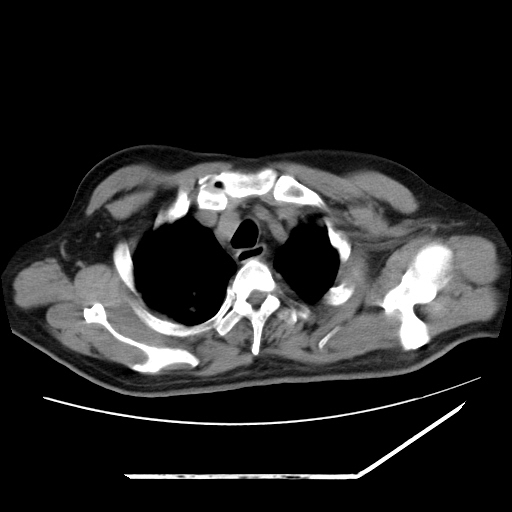

男,57,畏寒,发热

两肺野多发大小不一高密度灶,纵膈内见肿大淋巴结,要考虑转移瘤可能。双侧胸腔少量积液。

双肺多发结节样病灶,部分内见透光区,纵隔内见淋巴结肿大。结核临床如有畏寒,高热,白细胞增高首先考虑迁徙性肺脓肿(多是金黄色葡萄球菌感染)。

注意除外转移瘤。